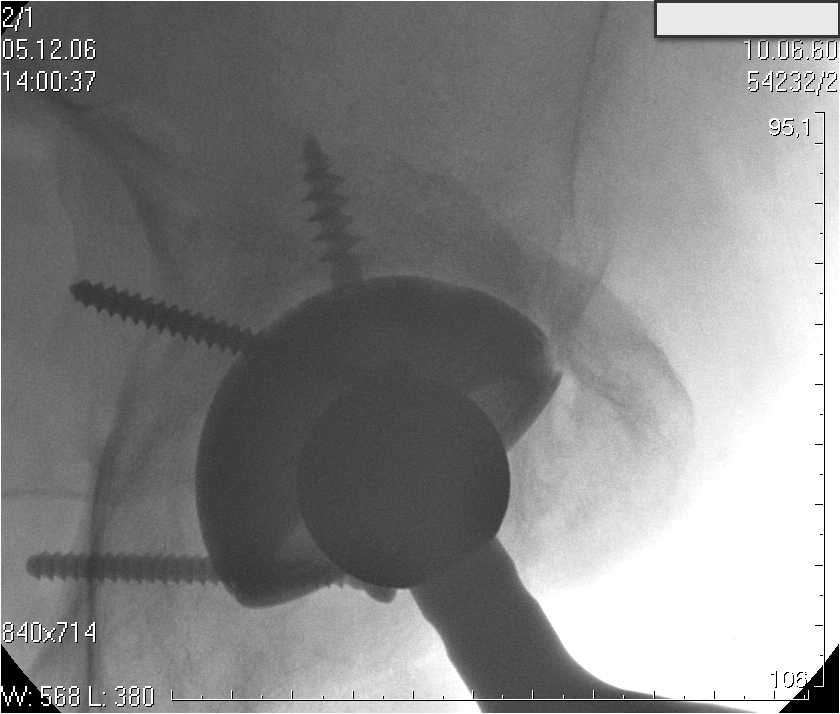

Уважаемые коллеги.В 3 Центральный Военный Клинический Госпиталь имени А. А. Вишневского, что в Красногорске, Московской области, в отделение эндопротезирования крупных суставов поступил пациент 1960 года рождения Жалобы при поступлении: на боли в области левого тазобедренного сустава (больной указывает на точку расположенная в середине условной линии между седалищным бугром и большим вертелом), усиливающиеся в начале ходьбы, при опоре на левую ногу с иррадиацией болей по наружной и наружно-задней поверхности левого бедра, левый коленный сустав; снижение объема движения в левом тазобедренном суставе, снижение опорной способности левой нижней конечности, хромоту на левую ногу, необходимость использования дополнительной опоры (костыли) при ходьбе, снижение объема двигательной активности из за болей в суставе.В анамнезе: Со слов больного, согласно медицинских документов, в 1989 году получил травму левой нижней конечности: закрытый перелом левой вертлужной впадины с центральным вывихом головки левой бедренной кости. Лечился консервативное. В процессе лечения сформировался посттравматический артроз, укорочение левой нижней конечности до 5 см. 25.04.2005 года в Подольском Окружном Госпитале Министерства Обороны выполнено: одномоменто, остеосинтез заднего края вертлужной впадины фрагментом резецированной головки бедренной кости и тотальное эндопротезирование левого тазобедренного сустава бесцементным эндопротезом "VERSIS ET" с бесцементной чашкой TRILOGY. Послеоперационный период осложнился ранним нагноением области эндопротеза, в результате санаций очага инфекции и антибиотикотерапии, активного промывного дренирования антисептиками, послеоперационная рана зажила. После операции, со слов больного, через два месяца в полном объеме стал нагружать левую нижнюю конечность. В течение полгода, после операции чувствовал себя вполне удовлетворительно. С марта 2006года стал отмечать появление болей в области тазобедренного сустава, то в области паха, то в области левой ягодицы. С августа месяца отмечает те жалобы, с которыми он сейчас к нам обратился. Температура тела, после заживления раны, нормальная. В анализах крови, лейкоциты около 7 тыс, формула нормальная, СОЭ 12 мм ч. Локально: при осмотре обеих нижних конечностей, анатомическая ось конечности не нарушена; отмечено относительное укорочение левой н\конечности на 1.5 см., гипотрофия мышц левого бедра 3 см, голени 2 см, симптом. Объем движений в тазобедренных суставах: правый~ сгибание- 60 гр, разгибание-180 гр ,отведение- 35 гр, левый~ сгибание- 110 гр , разгибание-170 гр , отведение-15 гр. Контуры других суставов н/конечностей обычные, объем движений в них не страдает. Пульсация на артериях конечностей удовлетворительная. Неврологические нарушения конечностей отсутствуют, рефлексы на обеих н/конечностях одинаковые, чувствительных нарушений нет. Осевая нагрузка на левую нижнюю конечность вызывает боль в точке расположенная в середине условной линии между седалищным бугром и большим вертелом. Отмечается пигментация и пастозность нижней трети обеих голеней и стоп, характерная для посттромботической болезни. На Цветном дуплексном сканировании сосудов нижних конечностей: Нестенозирующий атеросклероз обеих бедренных и подколенных артерий . Гемодинамически значимых препятствий кровотоку в магистральных артериях ног не выявлено. Глубокие и поверхностные вены нижних конечностей проходимы. Умеренная недостаточность клапанов подколенных вен. Данных за тромбоз глубоких вен на момент осмотра не получено.А вот что пишет наш рентгенолог: На серии рентгенограмм области левого тазобедренного сустава определяется тотальный бесцементный эндопротез. Вокруг тени чашки эндопротеза определяется ободок остеорезорбции. Кроме того, визуализируется деформированный костный винт фиксирующий консолидированный отломок вертлужной впадины, вплотную прилегающий к тени чашки эндопротеза. Заключение: Рентгеновские признаки нестабильности чашки тотального эндопротеза. Лучевая нагрузка: 6 мЗв. У нас в отделении разошлись мнения: начальник мой утверждает, после сравнения снимков, принесенных больным от августа и октября 2006года и наших рентгенснимков, что у больного нет нестабильности вертлужного компонента, и что надо назначит курс консервативной терапии: препараты кальция, миакальцик, увеличить осевую нагрузку на левую нижнюю конечность, ЛФК направления на укрепление мышц бедра, ягодиц, физиолечение. А я утверждаю, что у больного клиника нестабильности вертлужного компонента, и необходима ревизия вертлужного компонента, не исключено даже наличие инфекции под чашкой эндопротеза (не смотря на отсутствие клинических признаков инфекции). В результате проводимой консервативной терапии, боли у больного усилились. Помогите рассудить нас, мы готовы выслушать ваши мнения по этому поводу. С уважением Батал Шушания.3 ЦВКГ имени А. А. Вишневского